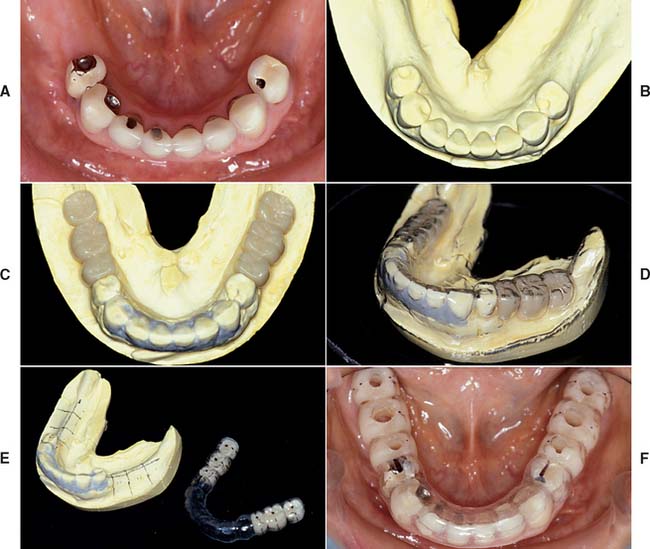

Accurately mounted diagnostic casts (see Chapter 2) are essential for treatment planning. They are used to study the remaining dentition, evaluate the residual bone, and analyze maxillomandibular relationships. They can be helpful to the surgeon for fixture placement. A diagnostic waxing is performed on the cast or on a duplicate. Proposed fixture installation sites are checked for proper alignment, direction, location, and relation to the remaining dentition. The waxing helps determine the most esthetic placement of the teeth to be restored and the potential for functional speech disturbances. After adjustments and the diagnostic waxing are completed, a resin template can be made from the cast to guide the surgeon during implant placement (Fig. 13-9). Diagnostic waxings and surgical templates are essential when implants are planned as part of a full-mouth reconstruction or when the anterior esthetic zone is restored (Fig. 13-10).

Fig. 13-9 A, Patient with bilateral missing posterior teeth planned for posterior implant-supported restorations. B, Diagnostic cast. C, Diagnostic denture tooth arrangement to simulate three-unit fixed prostheses on each side of the mandible. D, Vacuumed matrix formed over the cast with 1.5-mm (0.060-inch) thermoplastic sheet. E, The matrix is marked with the most appropriate implant locations and alignments and then removed from the cast. F, The completed surgical guide with holes drilled to guide the surgeon during implant site preparation.